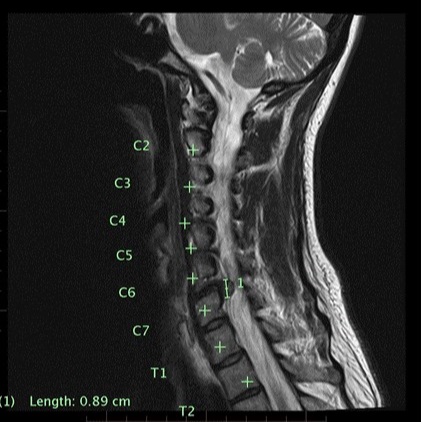

Symptom onset was insidious, and the patient attributed this to poor posture sitting at work. Her symptoms exacerbated 2 weeks after the onset after she fell on steps. An MRI and CT scan organized by the treating General Practitioner (GP) identified a disc herniation at C6/7 (Figure 2). At the time of the initial consultation, the patient was unable to work due to her symptoms and she was worried about the financial implications. She was married with 2 teenage children and prior to injury she enjoyed yoga and walking. The patient was fearful of her diagnosis and long-term implications, and she was quite distressed by other findings on her imaging reports, such as, “multi-level disc degeneration” and “degenerative disc disease”. The patient had attended for other interventions such as chiropractic, massage, acupuncture and Bowen therapy, which had not afforded symptom relief nor provided a long-term strategy for managing her condition. She was using pain medication as directed by her GP, which included paracetamol, Lyrica and Celebrex. An appointment with a neuro-surgeon was pending.

Figure 2. MRI of the cervical spine.

Radiologist report indicated multilevel established cervical disc degenerative changes together with a sizeable broad-based right posterolateral disc extrusion at C6/7 that obscured and likely significantly compressed the exiting intraspinal right C7 nerve root.

Loss of triceps reflex and weakness in the C7 myotome identified during the physical examination combined with the MRI evidence of a C6/7 disc extrusion supported a hypothesis of C7 cervical radiculopathy. Due to the presence of a C6/7 disc extrusion and the fact that the patient gained relief from non-steroidal anti-inflammatory medication, it was hypothesized an inflammatory process was the main cause of her symptoms (5). Neurodynamic and neural tissue provocation testing were indicative of neural tissue mechanosensitivity. The SFO identified an elevated level of concern relating to the long-term prognosis. Interpretation of the NDI and PSFS identified the patients presentation was having a significant impact.